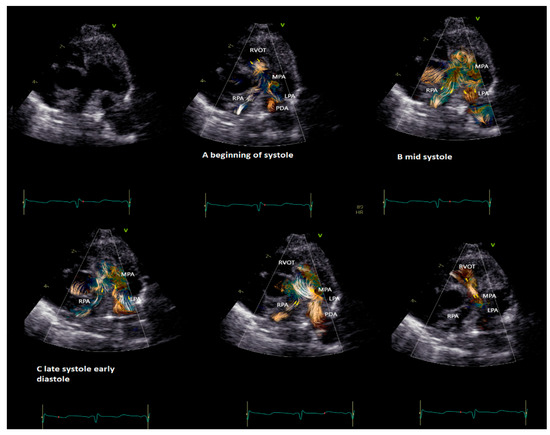

Practical examples of differences among physiological and pathological aortic vortices are provided in Figure 5. In Figure 5a, a physiological vortex is shown, while in Figure 5b, an example of a big vortex in the dilated ascending aorta of a child with a bicuspid aortic valve with moderate stenosis has been provided. The propagation of the vortex in the aortic arch in physiological condition and in a child with bicuspid aortic valve with moderate stenosis is shown in Figure 6. In the example, it appears clear that the vortex of the healthy patient (Figure 6a) occupies a smaller area than the pathological vortex and is localized on the ventral surface of the aortic arch, below the first two epi-aortic branches. On the contrary, the vortex of the child with bicuspid aortic valve valvular stenosis (Figure 6b) is located proximal to the epi-aortic branches and occupies the great part of a dilated transverse arch.

Figure 5. Vortex in the aorta of a healthy child (a) and in a patient with a bicuspid aortic valve causing moderate stenosis (b) The vortex develops at the end of diastole in both patients, but while in the healthy subject (a), physiologically we have a vortex inside the aortic root (AoRoot), in the child with bicuspid aortic valve (b), due to the stenosis, the vortex develops more distally, above the sinus-tubular junction, and it is bigger than its healthy counterpart. AoRoot = aortic root, LA = left atrium; LV = left ventricle; MV = mitral valve; RA = right atrium; RV = right ventricle.

Figure 6. Vortex in the aortic arch in a healthy child (a) and in a 3-year-old child with moderate aortic valve stenosis (b). It appears clear that the vortex of the healthy patient (a) occupies a smaller area than the pathological vortex and is localized on the ventral surface of the aortic arch, below the first two epi-aortic branches; on the contrary, the vortex of the child with valvular stenosis (b) is located proximal to the epi-aortic branches and occupies the great part of a dilated transverse arch.